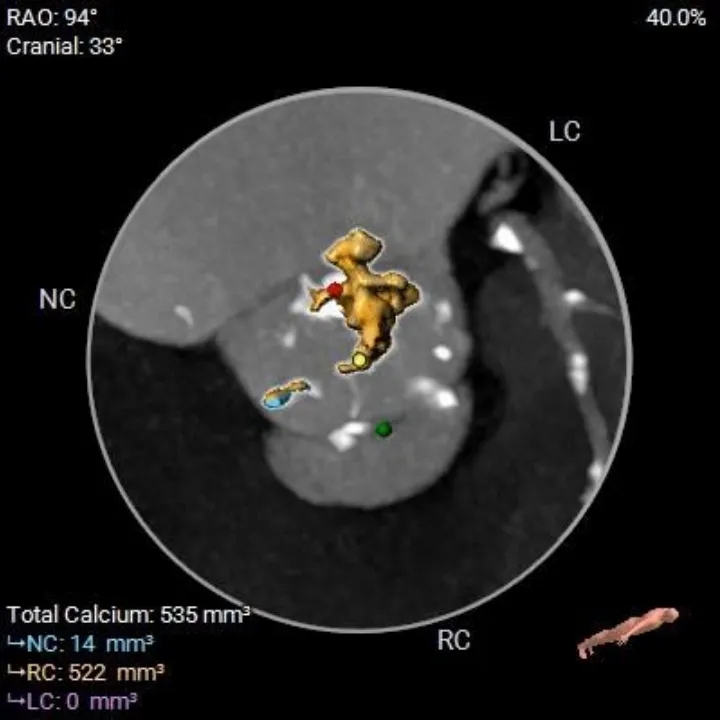

钙化积分

535

横列式Type0型二叶瓣,瓣环内径23.8mm

瓣叶显著增厚、重度偏心钙化

升主扩张

瓣上限制较重,可见明显左窦瓣叶偏心钙化,限制最重区域为瓣上4-8mm。